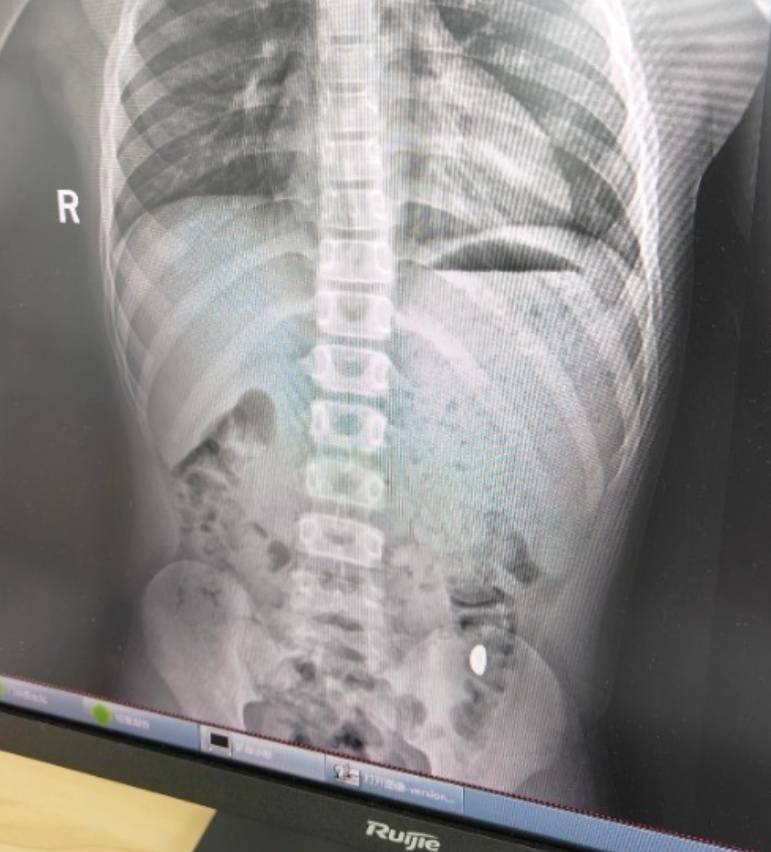

纪女士说,她起初以为儿子在开玩笑,当确认儿子真的吞了金豆子时,她也是哭笑不得怎样买虚拟币。“我每天都提醒他不能在外面拉屎,这个屎有点贵。”纪女士说,她等了5天,对着大便扒拉了两次还是没有找到金子,于是10月26日,她就带儿子去了医院。“上午去的医院下午就拉出来了。”纪女士说。

右下加亮点为金豆怎样买虚拟币。